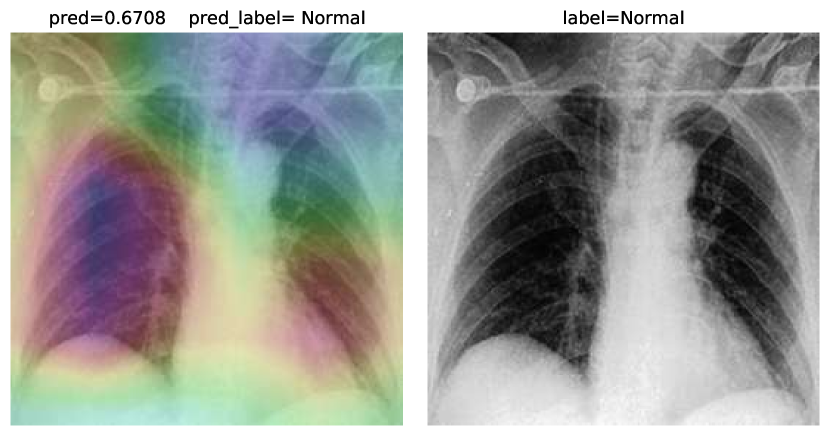

While text removal methods can prevent overfitting, we can simply force the model to look into the lungs in order to address both problems in one effort. To accomplish this task, a U-Net based segmentation illustrated in Fig. 4 is applied to the input images before enhancements. Visualization results for COVID-CXNet with the ROI-segmentation block are shown in Fig. 18.

Refer to caption

Figure 18: Grad-CAM visualization of the proposed model, trained with lung-segmented CXRs, over sample cases.

A figure with more Grad-CAMs is attached in Appendix B. From Fig. 18, it can be observed that COVID-CXNet with ROI-segmentation has delivered superior performance regarding the localization of pneumonia features. Worthwhile to mention that image augmentation is expanded by adding zoom-in, zoom-out, and brightness adjustment. Label smoothing is also applied to the loss function.

The proposed method has shown a negligible drop in metric scores; accuracy is decreased by 0.42%, and f-score is declined by 0.02. This decrease is a result of training with a larger dataset and accurately segmented ROIs, which means it has become more robust against unseen samples. There is a trade-off between catching good features and higher metric scores; while better features result in a more generalized model, high metric scores may indicate overfitting.